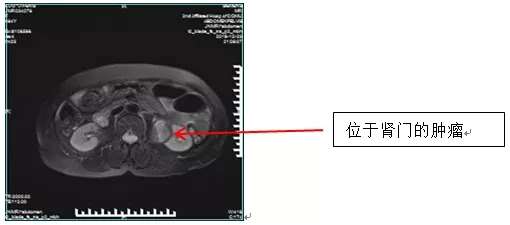

患者入院后,我院CT及MR检查提示左肾肾窦-肾门-左侧腰大肌旁见团块状脂肪密度为主影,大小约40×38mm,性质考虑:血管平滑肌脂肪瘤或脂肪瘤?肾血管平滑肌脂肪瘤是由异常增生的血管、平滑肌及脂肪组织按照不同比例构成的,是一种良性肿瘤。

但它也同时是体内一枚定时炸弹,当较大体积的肾血管平滑肌脂肪瘤突然破裂时,患者会出现腰腹疼痛和血尿等症状,严重的大出血患者甚至有休克症状。罗女士瘤体位置特殊,直接位于肾门,肾门区域有密集的肾静脉、动脉及肾盂输尿管走形,如果要保肾手术,分离肿瘤的过程稍有不慎有大出血、漏尿可能。并且切除肿瘤后肾脏创面张力较高,肾血管及输尿管均位于创面内,缝合难度十分大。因此,当地医院都不愿接受这样复杂的手术。